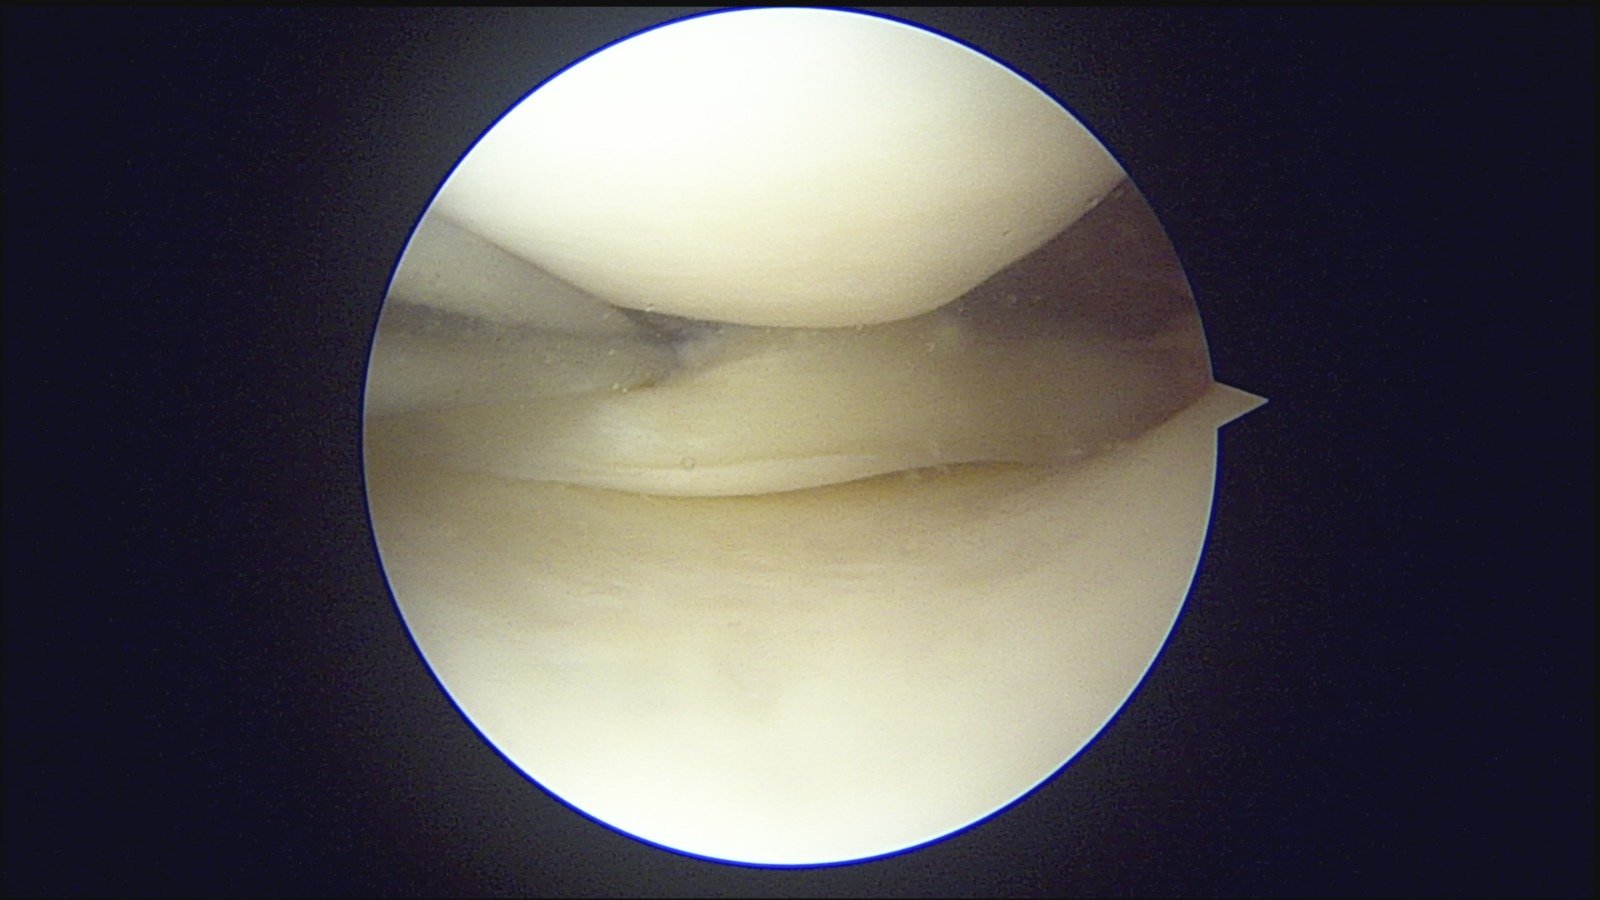

GalleryShoulder rotator cuff repair Meniscus root repair Meniscus repair Bankart repair for recurrent shoulder dislocation ACL reconstruction Machines Instruments